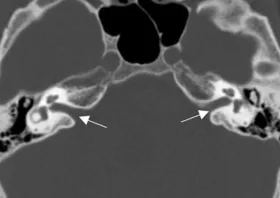

A Steady-state free precession (SSFP) axial image showing the olfactory nerves (arrows).

Coronal plane image of cribriform plate (asterisks).

A Steady-state free precession (SSFP) axial image showing the optic nerves (arrows).

Optic canal (asterisks) and superior orbital fissure (arrow)

Axial CT of superior orbital fissure (arrows) and optic canal (asterisks).

Axial CT of foramen rotundum (asterisks).